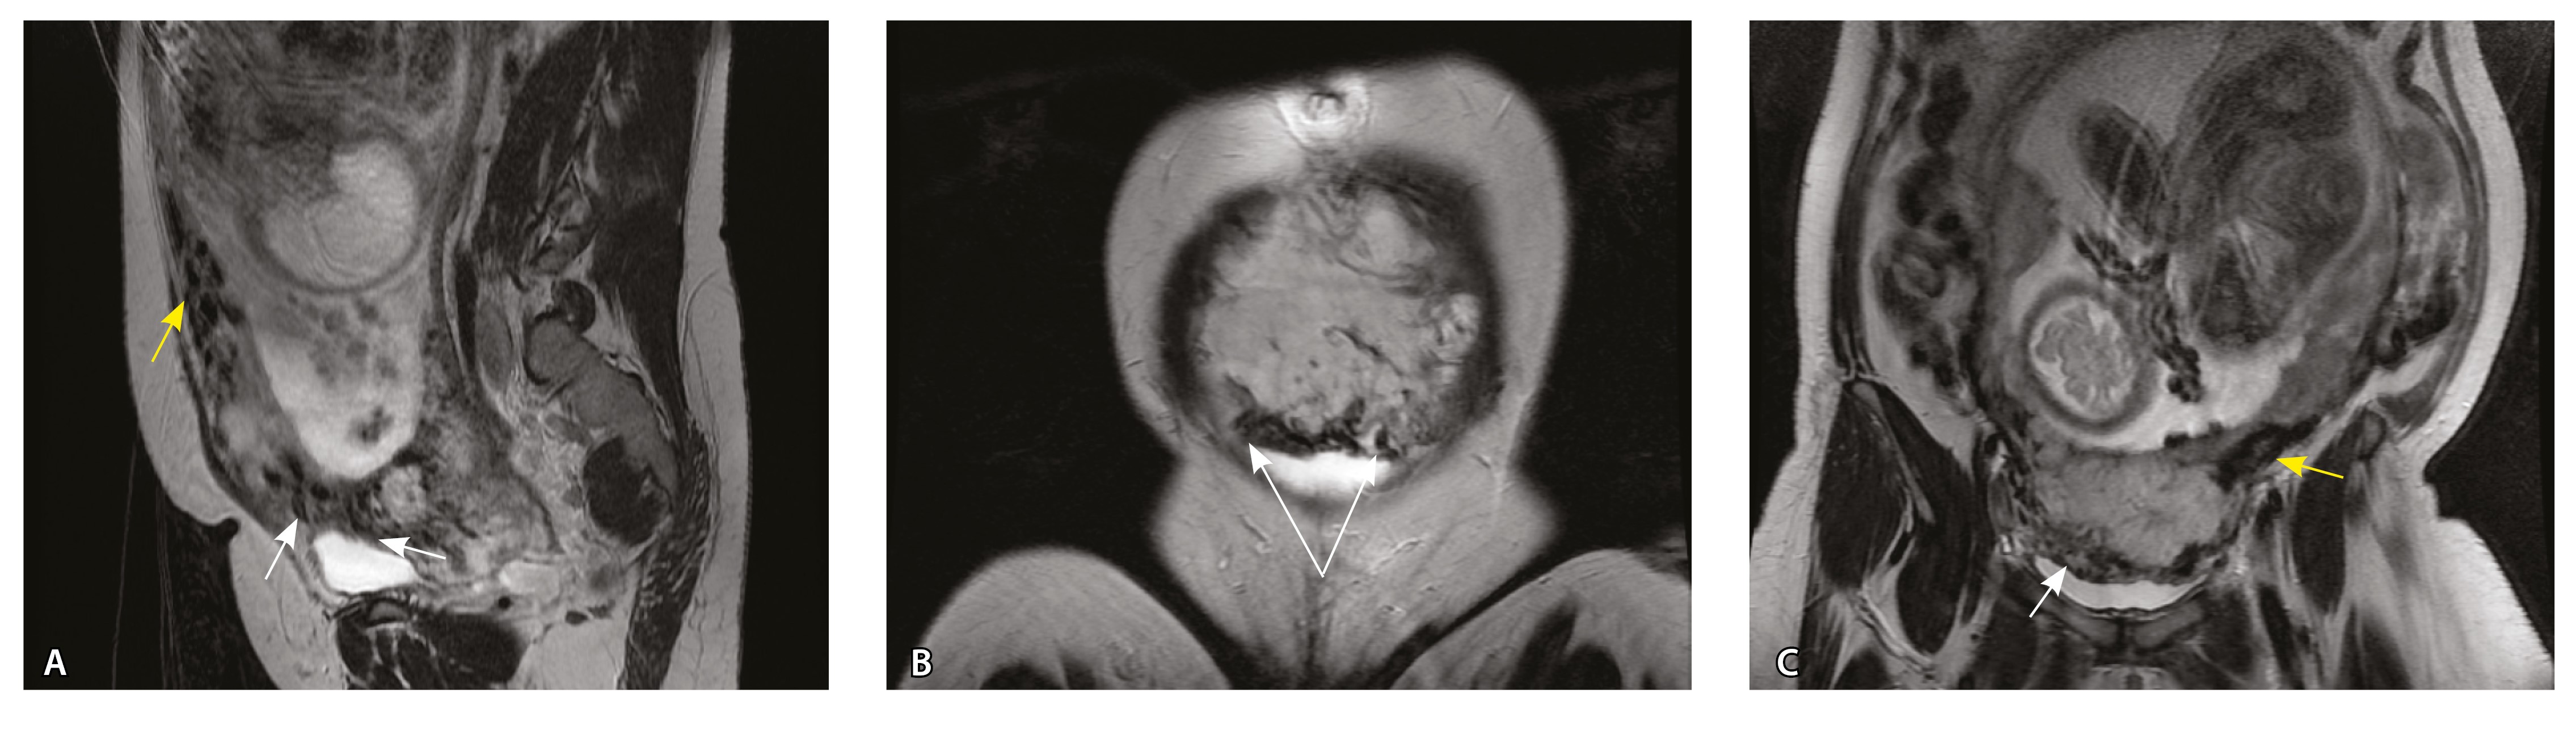

Сосуды 4-го типа. Наличие крупных извитых анастомозирующих сосудов, преимущественно по поверхности матки (в составе серозной оболочки матки) в сочетании с выраженным истончением нижнего сегмента матки (рис. 10).

Рис. 10. Беременность 33 недели, pl. percreta, PAS 3a по FIGO. На магнитно-резонансных томограммах в режиме Т2-взвешенного изображения в сагиттальной (A) и фронтальной (Б, В) плоскостях определяется внутриматочная гиперваскуляризация (желтые стрелки) и гиперваскуляризация в области выраженно истонченного нижнего маточного сегмента, с наличием многочисленных анастомозирующих сосудов по поверхности матки (белые стрелки); стенка матки в данной области представлена ретроплацентарными сосудами

Главным отличием крупных сосудов в составе серозной оболочки является то, что морфологически они находятся в пределах стенки матки. Об этом свидетельствует наличие в операционном материале тонкого поверхностного слоя мезотелия, отделяющего матку от брюшной полости (рис. 11). Его невозможно визуализировать методом МРТ из-за особенностей метода и толщины получаемых срезов.

Рис. 11. Сосуды 4-го типа при гиперваскуляризации стенки матки при патологической инвазии: А – крупный сосуд в составе серозной оболочки матки: справа видны единичные цитотрофобластические клетки (стрелки), не достигающие стенки артерии (иммуногистохимическое исследование, маркер цитокератин 8; × 50); Б – крупные сосуды в составе серозной оболочки: наличие внутреннего слоя эндотелиоцитов (иммуногистохимическое исследование, маркер СD34; × 50)

На микропрепаратах васкуляризация серозной оболочки представлена множеством крупных сосудов, идущих в разных направлениях и анастомозирующих друг с другом. Возможно, имеются артериовенозные соустья. На серийных срезах также видно, что в стенках артерий трудно различимы два слоя миоцитов (продольный и поперечный). Со стороны адвентиции они окружены толстым «футляром» из грубоволокнистой голубой ткани (при окраске по Маллори). Она проникает в стенку артерий, замещая мышечный слой (рис. 12).

Рис. 12. Истончение миометрия; в составе серозной оболочки видна крупная артерия, окруженная плотной соединительной тканью. А – cосуды в составе серозной оболочки (окраска по Маллори; × 200), не дифференцированная на мышечные оболочки стенка артерии, справа – вена, оба сосуда покрыты фиброзной оболочкой, внизу виден слой мезотелия в составе серозной оболочки; Б – серийный срез тех же сосудов при окраске на выявление эластических волокон, сосуд с соединительнотканной муфтой (окраска по Вейгерту; × 50): определяется полная дезорганизация эластичного материала в стенке; стрелкой указан мезотелий (аналог pl. increta, PAS 2 по FIGO)

Эластический каркас представлен сетью тонких волокон, без концентрации на внутреннюю и внешнюю мембраны. Однако маркер СD34 констатирует сохранение эндотелия, что свидетельствует о том, что по артериям циркулирует кровь, не сворачиваясь (рис. 13).

Рис. 13. Самые крупные сосуды в пределах серозной оболочки стенки матки: А, Б – серийные срезы артерии; × 50. При окраске по Маллори (А) видна тонкая полоска мезотелия (черная стрелка), слабо дифференцированная мышечная стенка артерии, вокруг нее – плотная коллагеновая оболочка (желтая стрелка), в просвете определяются тромботические массы. При окраске по Вейгерту (Б) наблюдается полная потеря внутренней и внешней эластических мембран

Анализ частоты встречаемости сосудов 4-го типа при различных степенях приращения плаценты (рис. 14) показал: при плотном прикреплении плаценты (gr 2) и поверхностном приращении (gr 3) сосуды данного типа не выявлены, при pl. increta (gr 4) частота встречаемости незначительная – 16,7%, а при глубокой инвазии плаценты (pl. percreta, gr 5) сосуды этого типа преобладают (р < 0,001, хи-квадрат Пирсона).

Сосуды 4-го типа встречались как при pl. increta (16,7%) (PAS 2 по FIGO), так и при pl. percreta (100%) в пределах серозного слоя матки (PАS 3a по FIGO). Обнаружено наличие крупных извитых анастомозирующих сосудов, преимущественно по поверхности матки, в сочетании с выраженным истончением рубца от КС. Главное отличие сосудов этого типа – локализация в пределах серозного слоя матки, с наличием тонкого поверхностного слоя мезотелия на микропрепаратах по их поверхности. Этот феномен можно объяснить тем, что в случае прикрепления трофобласта и затем плаценты к рубцу от КС при прогрессировании беременности плацента оказывает паракринное влияние в том числе посредством факторов ангиогенеза, в результате чего нельзя исключить рост сосудов из бассейнов маточных артерий с целью обеспечения трофической функции матки и сохранения беременности. Указанный патогенетический механизм также подтверждают описанные в литературе случаи брюшинной беременности [17]. Кроме того, нельзя исключить, что локальная ишемия стенки матки в области врастания может способствовать увеличению ангиогенеза и васкулогенеза. При выполнении МРТ невозможно достоверно визуализировать серозный слой матки из-за его малой толщины, поэтому создается впечатление о локализации сосудов за пределами стенки матки. По данным патоморфологического исследования, для этого типа характерно наличие крупных сосудов, анастомозирующих друг с другом. В стенках артерий трудно различимы 2 слоя миоцитов, по наружной поверхности сосуды окружены толстым «футляром» из грубоволокнистой соединительной ткани, которая проникает в стенку артерий и замещает мышечный слой. Эластический каркас представлен сетью тонких волокон, без концентрации на внутреннюю и внешнюю мембраны. Генез возникновения таких сосудов до конца не изучен. В ряде исследований, посвященных беременности, расположенной в проекции рубца от КС, отмечается наличие артериовенозных соустий по типу мальформации в данной области даже на ранних сроках беременности, которые, возможно, продолжают функционировать и на более поздних сроках и становятся еще более полнокровными [18–20].